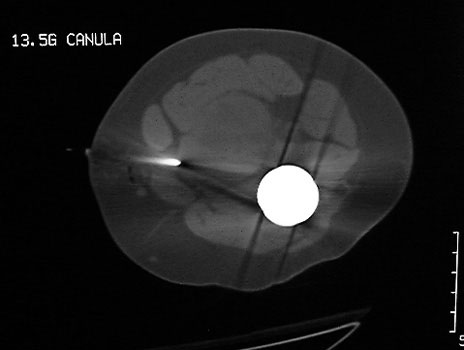

CT guided biopsy

Mass in patient with modular endoprosthesis placed after resection of femur for osteosarcoma. Axial (fig A) and coronal reformatted images (fig B) clearly demonstrate mass adjacent to modular endoprosthesis. 14 gauge core needle biopsy performed under CT guidance (fig C) demonstrated recurrent osteosarcoma